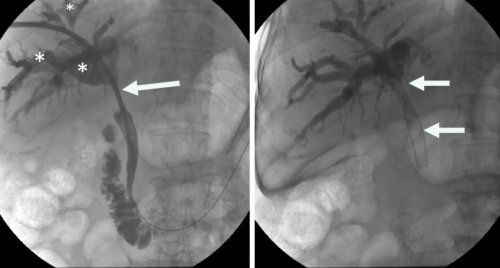

İzmir Ekonomi Üniversitesi Medical Point Hastanesi Tıbbi Direktör Ahmet Memiş'in öncülüğünde, farklı tıp disiplinlerinin işbirliğiyle geliştirilen hibrit yaklaşımlar, endoskopik, gastro ve girişimsel radyoloji teknikleri bir araya getirerek karmaşık safra yolu sorunlarında çığır açıyor. Bu yenilikçi yöntemler, hastaların iyileşme süreçlerini hızlandırırken, daha az travmatik operasyonlarla tedavi imkanı sunuyor. Prof. Dr. Ahmet Memiş'in önderliğinde uygulanan bu yenilikçi yöntem, endoskopik teknikleri ve iğne ile giriş yöntemlerini tek bir operasyonda birleştiriyor. Bu sayede, daha önce tedavisi çok zorlu kabul edilen karmaşık safra yolu problemleri artık daha etkili ve minimal invaziv bir şekilde tedavi edilebiliyor. Hibrit yaklaşımların en önemli avantajlarından biri, hastaların bedenine minimum düzeyde zarar vermesidir. Büyük cerrahi kesilerin yerine, endoskopik, gastro ve girişimsel radyoloji yöntemler kullanılarak, iğne deliği kadar küçük girişimlerle operasyonlar gerçekleştiriliyor. Bu da hastaların ameliyat sonrası ağrılarını azaltıyor, enfeksiyon riskini düşürüyor ve hastanede kalış sürelerini kısaltıyor.

Prof. Dr. Ahmet Memiş, “Hibrit yaklaşım, sadece tedavi değil, aynı zamanda tanı sürecinde de önemli avantajlar sunuyor. Hekim, hastanın vücuduna dokunmadan, radyolojik görüntüleme teknikleriyle hastalıklar daha hızlı ve doğru bir şekilde tespit ediliyor. Bu da tedavi sürecinin daha etkin bir şekilde planlanmasına olanak sağlıyor. Farklı disiplinlerden uzman hekimlerin bir araya gelerek oluşturduğu sinerji, karmaşık safra yolu sorunlarında başarı oranını önemli ölçüde artırıyor. Bu sayede, hastalar daha hızlı iyileşme göstererek günlük yaşamlarına daha kısa sürede dönebiliyor. Geleneksel cerrahi yöntemlerde uzun iyileşme süreleri ve yoğun ağrılar yaşanırken, minimal invaziv yaklaşımlar sayesinde bu sorunlar ortadan kalkıyor. Hastalar, operasyon sonrası çok daha kısa sürede taburcu oluyor ve gündelik aktivitelerine hızla dönebiliyorlar. Bu da hem hasta konforunu artırıyor hem de sağlık sisteminin üzerindeki yükü hafifletiyor” dedi.